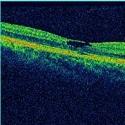

Idiopathic macular hole : unusual cause of vision loss

Hajji Chaimae, Rajae Daoudi

PAMJ. 2014; 18: 246. Published 26 July 2014